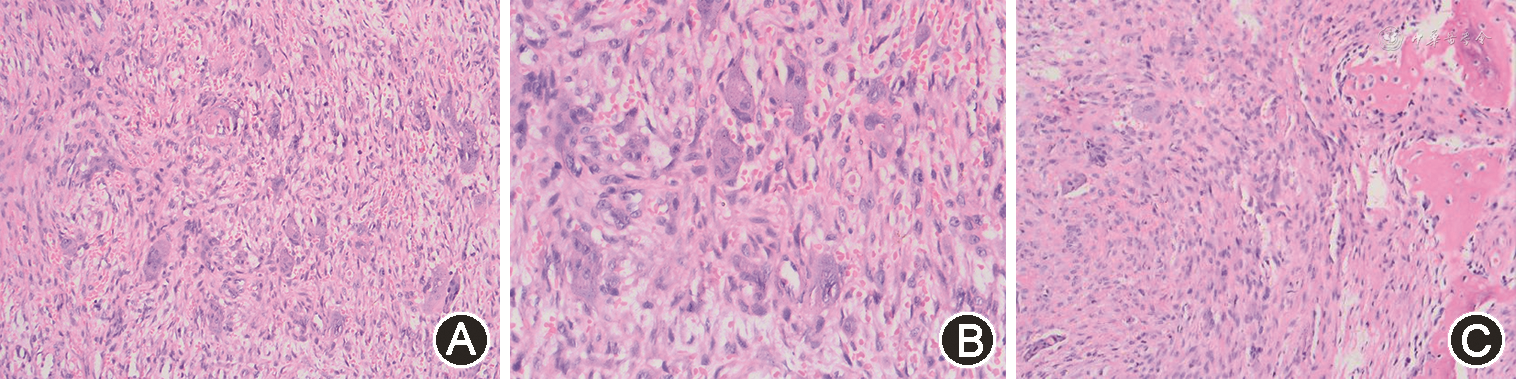

患者女,21岁,以“面部不对称半年余”为主诉于2019年2月10日就诊于蚌埠医学院第一附属医院口腔颌面外科。患者既往健康状况良好,无手术等特殊病史。专科检查示:颜面部不对称,右侧下颌角区可触及约3 cm×4 cm范围骨质膨隆,边界尚可,无压痛;左侧颞下颌关节区较右侧稍膨隆,无压痛;双侧颞下颌关节活动对称,开闭口运动时关节无弹响、压痛;下唇无麻木感,双侧颈部、颌下及颏下淋巴结未触及肿大;张口度3.6 cm,张口型正常。口腔内未见明显异常。曲面断层片显示:右髁状突及左、右下颌骨体部可见单房椭圆形囊状破坏区,边缘无切迹,透光区不明显(图1)。入院后行颌骨CT平扫时发现,双侧下颌骨体部、升支、髁状突、枕骨、蝶骨弥漫性骨质密度海绵质样增高伴多发骨质破坏(图2)。生化常规:总钙离子2.46 mmol/L,离子钙1.32 mmol/L,无机磷0.78 mmol/L。完善相关检查后,拟行下颌骨病变刮治术。术中右髁状突采用耳屏前切口,其他均采用口内下颌颊侧前庭沟切口。术中见病灶区骨质菲薄,内含巨大创腔,无明显分隔,内容物见大量息肉样物质,刮出部分内容物送冰冻检查,结果示梭形细胞增生性病变,倾向良性。而后彻底刮除肿物,并用稀碘液浸泡创腔。术后给予抗感染、消肿、止痛等对症治疗。术后1周出院,伤口一期愈合。病理示病变主要由增生的纤维结缔组织背景中散在多核巨细胞构成(图3A、3B)。间质为梭形纤维母细胞样细胞,并有成为结节的趋势。病灶内常有出血,周围可有骨样组织及骨小梁再生。破骨细胞样多核巨细胞多在新生骨周围或围绕出血区域分布(图3C)。两侧送检组织镜下图像一致。术后患者面型较前无明显变化,按照术后1、3、6、12个月随访,共随访12个月,术后12个月颌面部曲面断层片显示下颌骨病灶区较之前有新生骨质形成。

GCRG根据病变部位分为中心性和周围性,中心性一般是包含骨组织,而周围性一般只含有牙龈或黏膜等软组织。根据病变的形态学特征可分为侵袭性和非侵袭性,有研究表明,术后病理免疫组织化学有助于判断病变的生物学特性[7]。GCRG通常是结合发病年龄、临床检查、影像学检查、实验室检查和病理诊断等作出综合判断。GCRG的病理学特征主要是大量的梭形成纤维细胞增生,之间富含多核巨细胞,大小形态不一,间质伴出血,可有含铁血黄素沉着,与本例的病理切片结果高度一致。